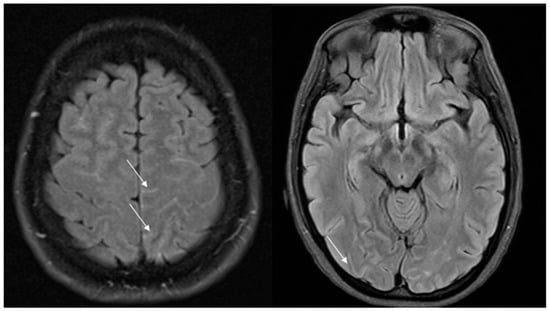

Complications of RCVS are more commonly observed in treatment-related RCVS than in primary RCVS [80]. Up to 81% of patients exhibit the following radiological abnormalities appearing days to weeks after the onset of thunderclap headache: cerebral ischemia (39%), intraparenchymal hemorrhage typically lobar in 20%, convexity subarachnoid hemorrhage in 34% and PRES in 38% [9] (Figure 5).

Cerebral vasoconstriction peaks 9–13 days after the initial thunderclap headache [15,81] and progresses with a distal-to-proximal pattern. This is the reason why ischemic and hemorrhagic complications have a different temporal distribution, occurring at varying times throughout the course of RCVS. Initially, ischemic lesions are due to perfusion deficits caused by altered arteriolar autoregulation and are small, peripheral and cortical (at the cortico-subcortical junction) [9,12]. After approximately two weeks, vasoconstriction of larger-caliber vessels leads to severe hypoperfusion, and the lesions are larger, wedge-shaped and watershed [9]. Vasoconstriction of small distal pial vessels may lead to reperfusion injury with subsequent vessel wall rupture and hemorrhagic stroke typically in watershed areas (as shown in Figure 5), which tends to manifest earlier (2–4 days after the headache attack) than the ischemic counterpart [82]. RCVS is also the leading cause of convexity subarachnoid hemorrhage in individuals aged < 60 years [83]. In these patients, thunderclap headache, FLAIR dot sign and multifocal vasoconstriction are diagnostic of RCVS [12]. A young age, a history of severe headache, chronic obstructive pulmonary disease requiring sympathomimetics (e.g., ephedrine), antidepressant use, a low Hunt Hess score or Fisher score and the involvement of multiple arteries including bilateral are independent predictors of RCVS-SAH [84].

As previously said, PRES and RCVS share their radiological features, as they are based on the same pathophysiological mechanisms, impaired cerebral regulation, blood–brain barrier disruption and endothelial dysfunction, leading to passive extravasation of fluids and proteins and resulting in vasogenic edema, which appears as hyperintensities on apparent diffusion coefficient (ADC) mapping.

Actually, MRI shows some differences between these two syndromes: In PRES, MRI typically shows symmetric vasogenic edema in the parieto-occipital regions, affecting both the subcortical white matter and the overlying cortex [22]. In contrast, PRES associated with RCVS is more often asymmetric. Additionally, hemorrhages and, less commonly, ischemic lesions have been described in PRES. The primary hemorrhagic pattern in PRES consists of multiple minute foci of microhemorrhages, whereas in RCVS, the most common hemorrhagic patterns are cSAH and ICH [22].

Figure 5. An overview of the potential complications of RCVS in four different patients. (a) Posterior reversible encephalopathy syndrome appearing as hyperintense lesions on fluid-attenuated inversion recovery imaging (FLAIR); (b) ischemic strokes (arrow) highlighted by diffusion-weighted imaging (DWI); (c) convexity subarachnoid hemorrhage shown as the hypointensity, demonstrated by gradient echo imaging that indicates the presence of blood within the cortical sulci; (d) temporo-parietal and frontal lobar parenchymal hemorrhages. RCVS: reversible cerebral vasoconstriction syndrome. FLAIR: fluid-attenuated inversion recovery. DWI: diffusion-weighted imaging.